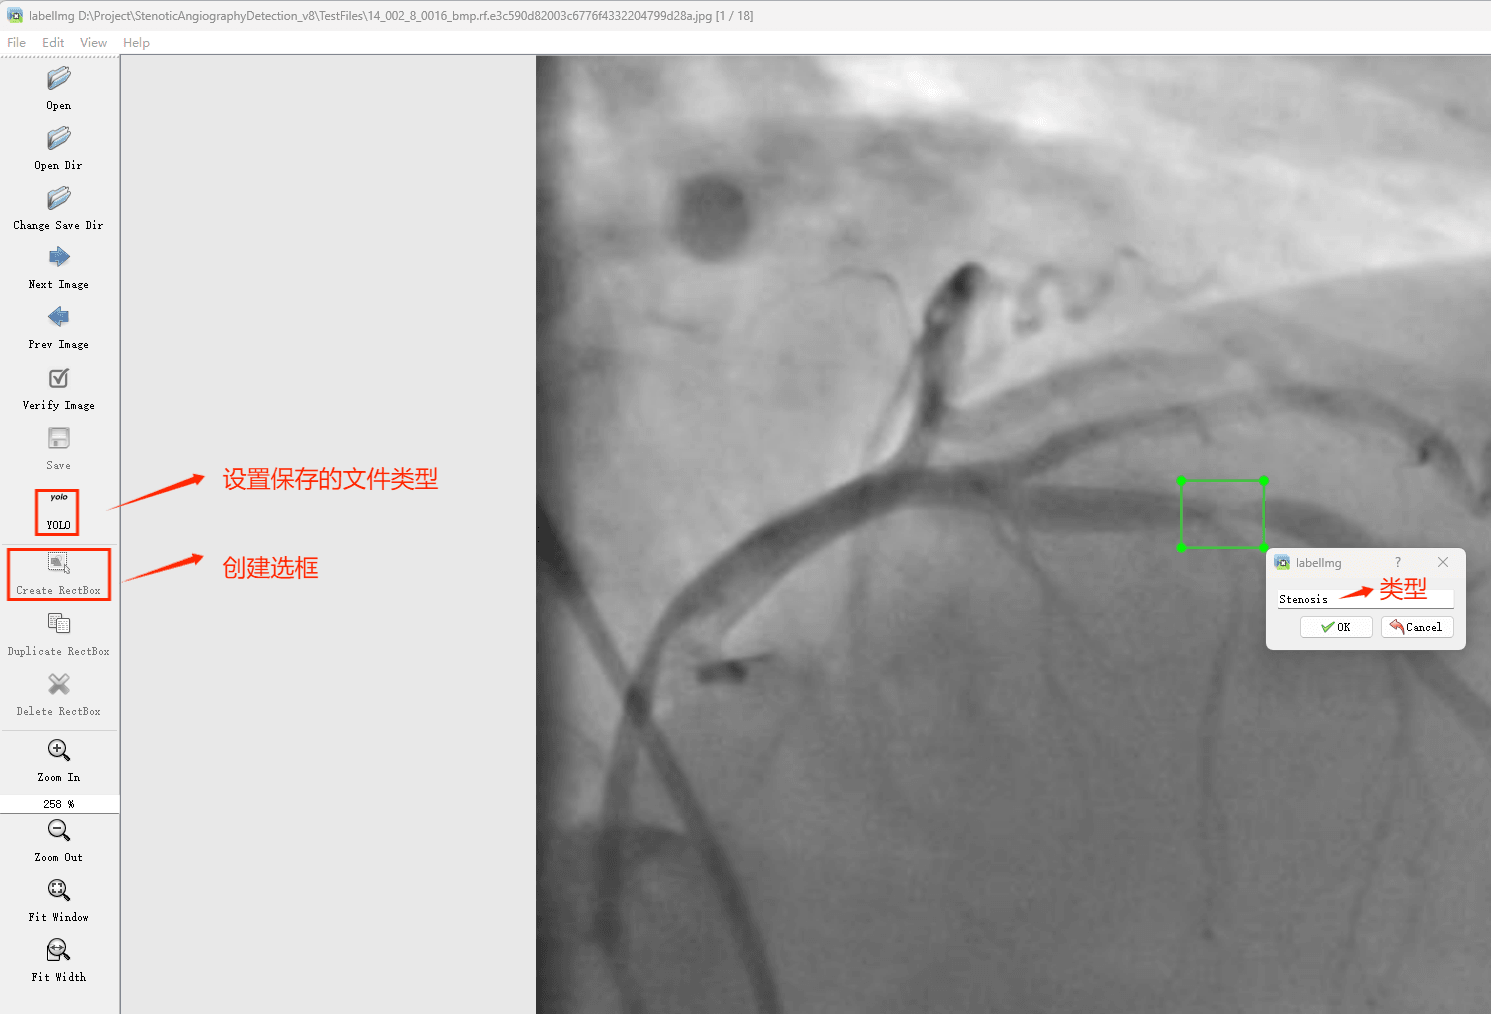

目标检测标注工具

(1)labelimg:开源的图像标注工具,标签可用于分类和目标检测,它是用python写的,并使用Qt作为其图形界面,简单好用(虽然是英文版的)。其注释以 PASCAL VOC格式保存为XML文件,这是ImageNet使用的格式。此外,它还支持 COCO数据集格式。

初识labelimg

打开后,我们自己设置一下

在View中勾选Auto Save mode

接下来我们打开需要标注的图片文件夹

并设置标注文件保存的目录(上图中的Change Save Dir)

接下来就开始标注,画框,标记目标的label,然后d切换到下一张继续标注,不断重复重复。